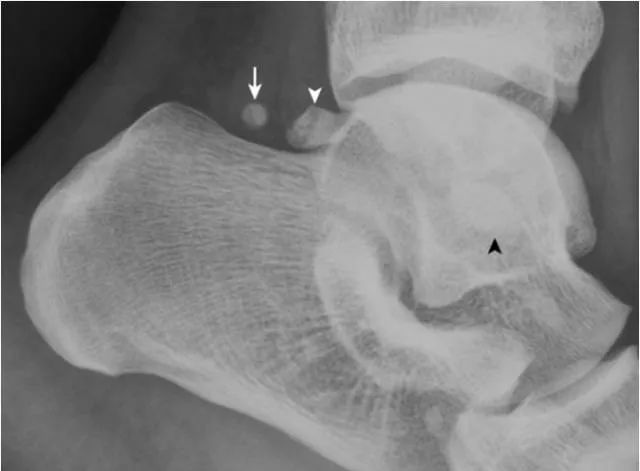

4.跟骨上副骨:

呈跟骨上方、三角骨(白箭头)后方骨性结节(箭),为正常变异。腓骨副骨(黑箭头)与距骨重叠。